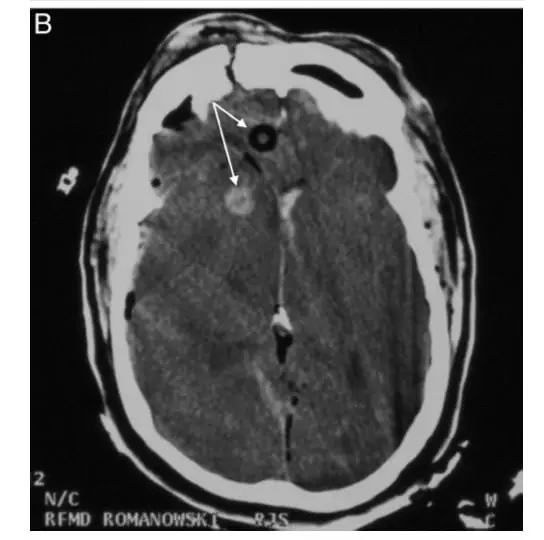

The third case was a 43-year-old male thrown head-first into a guardrail after a motorcycle accident. He had severe craniofacial injuries. Intubation was deferred prehospital secondary to concerns for severe facial trauma and C-spine immobilization. Instead, bilateral NPAs were placed. If the face is too damaged for endotracheal intubation, NPA placement is clearly contraindicated. Ultimately, his CT imaging showed comminuted anterior skull base fractures and intercranial placement of an NPA.5 (See the CT from this case below).